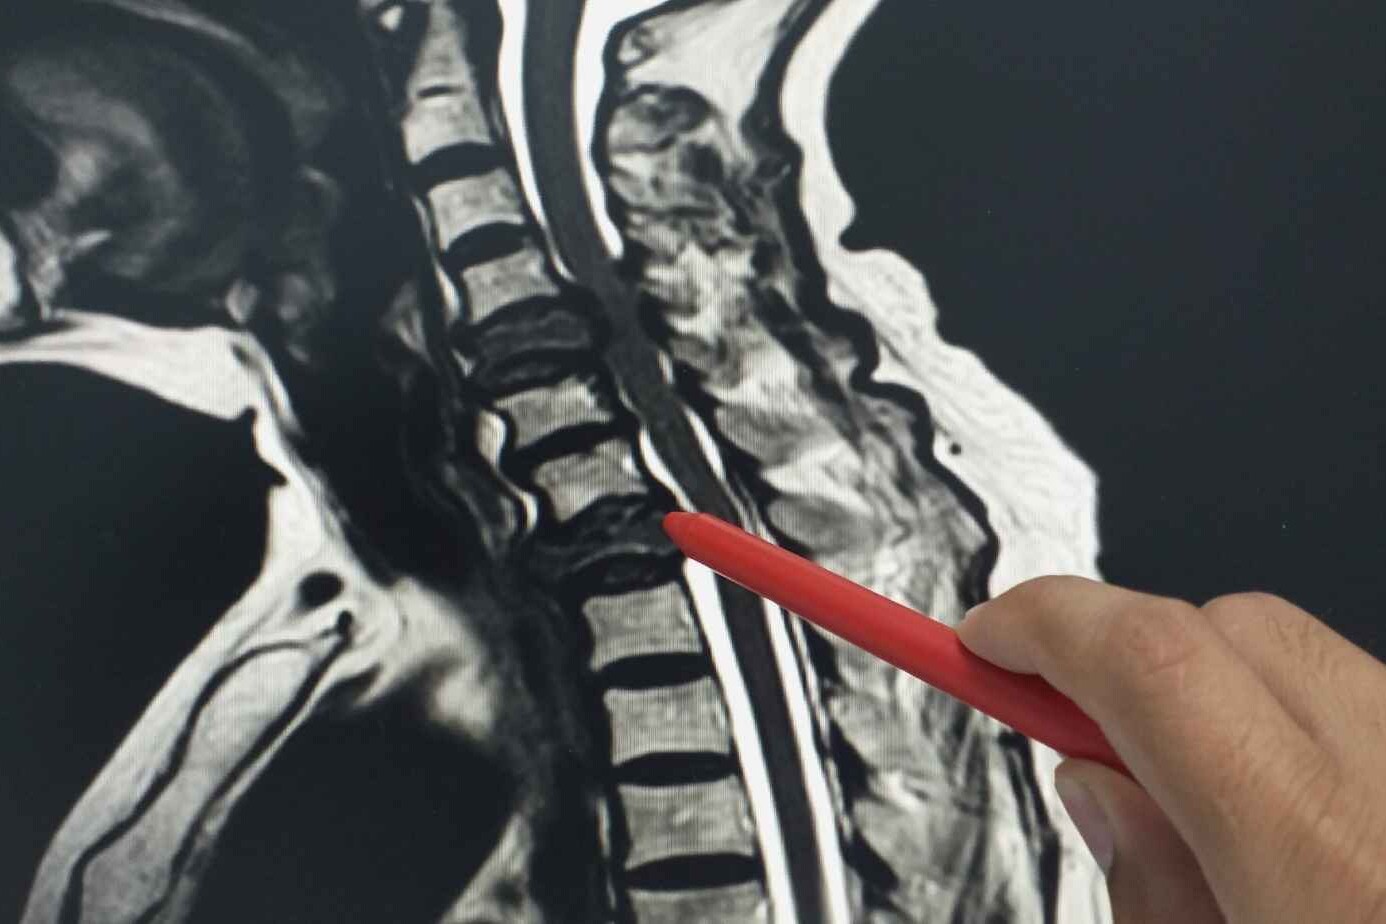

Spinal fusion surgery can be a daunting prospect, but it’s often a necessary step to relieve back pain and improve your quality of life. Understanding what to expect during the recovery process can help you mentally and physically prepare. Here, we will talk about the recovery process, rehabilitation, postoperative care, and resuming activities of daily living.